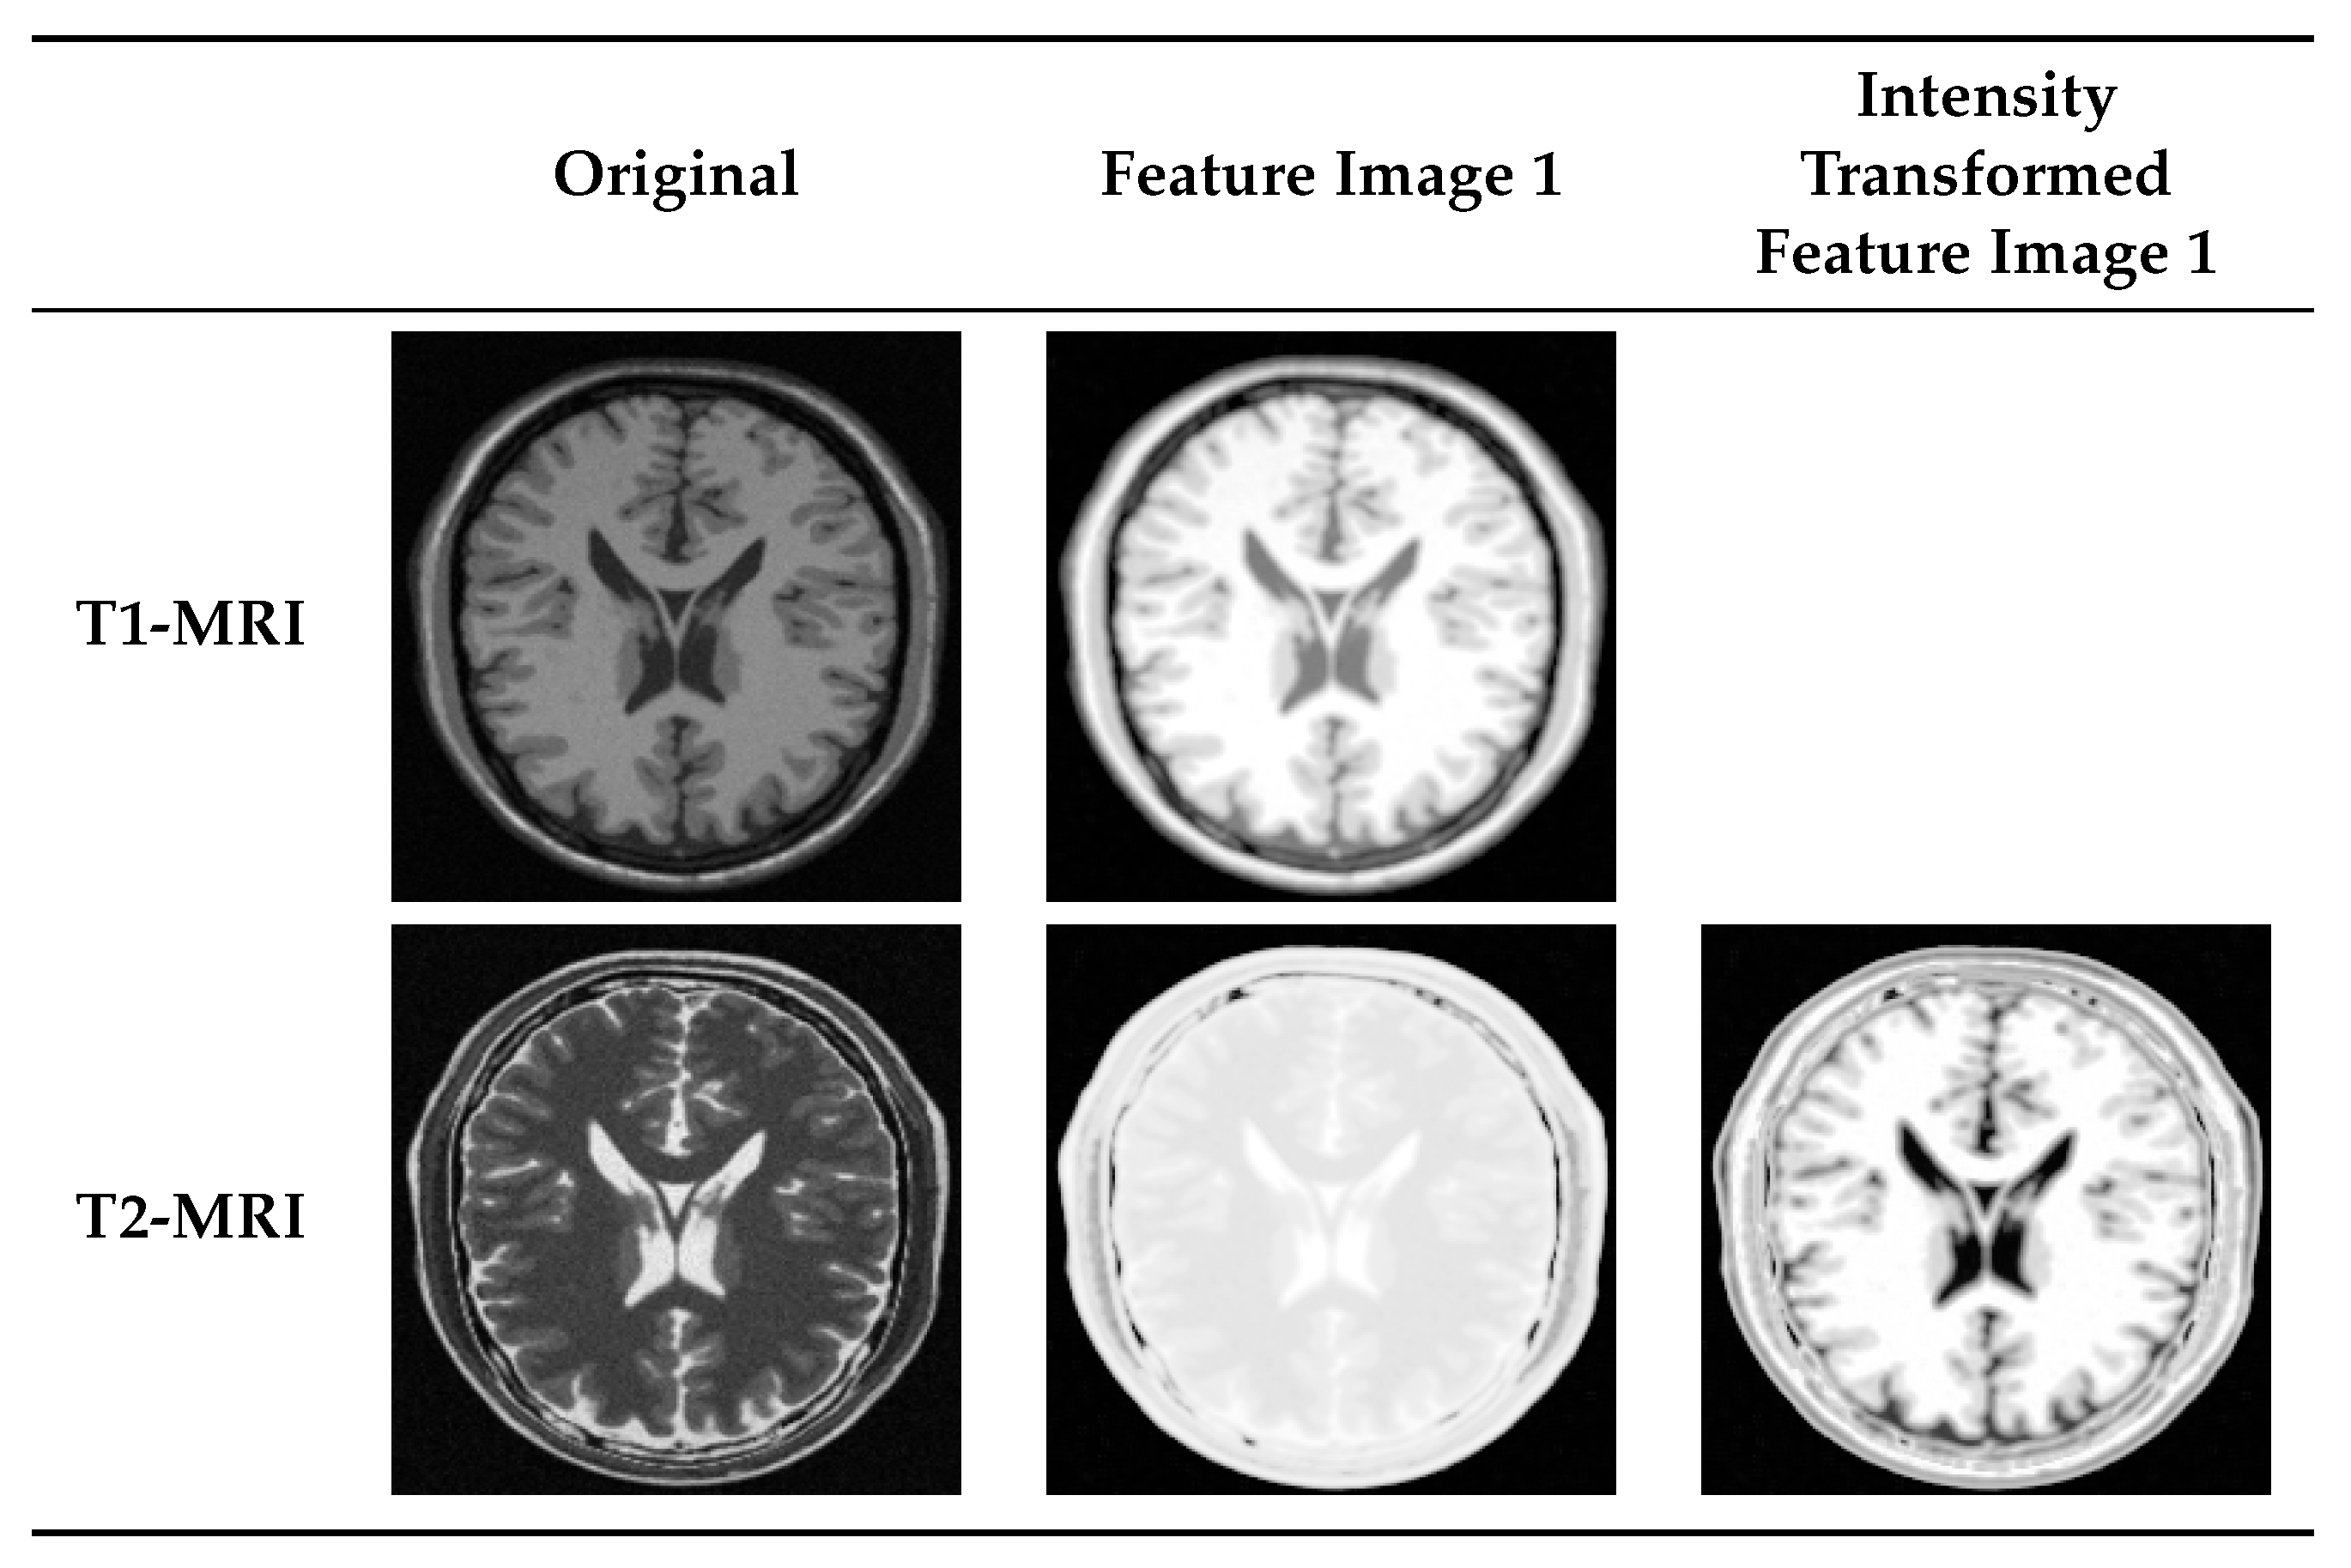

4.2. Multi-Modal to Mono-Modal Transformation

- Wachinger, C.; Navab, N. Entropy and Laplacian images: Structural representations for multi-modal registration. Med. Image Anal. 2012, 16, 1–17. [Google Scholar] [CrossRef] [PubMed]